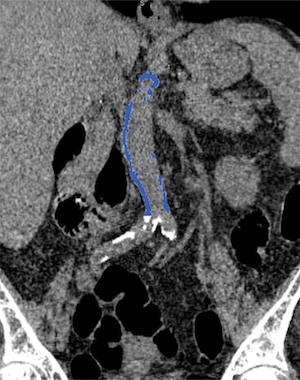

Dans le cadre de cette nouvelle étude, les chercheurs ont évalué la relation entre la calcification aortique abdominale identifiée par scanner et les événements cardiovasculaires survenus chez 829 patients asymptomatiques âgés en moyenne de 58 ans environ. Les patients avaient subi une coloscopie virtuelle de dépistage entre avril 2004 et mars 2005. Ils ont été en mesure de suivre les patients pendant 11 ans en moyenne pour voir s’ils avaient développé des événements cardiovasculaires indésirables tels qu'une crise cardiaque, un accident vasculaire cérébral, une insuffisance cardiaque congestive, voire un décès.

Sur les 829 patients, 156 (18,8%) ont fait l'objet d'un événement cardiovasculaire majeur. Les événements sont survenus près de sept ans après le scanner, en moyenne, et se sont matérialisés par une crise cardiaque chez 39 personnes et un décès chez 79 personnes. La calcification aortique abdominale identifiée par scanner a ainsi joué le rôle d'un puissant facteur prédictif d'événements cardiovasculaires futurs, surpassant le score de risque de Framingham. La calcification aortique abdominale était en moyenne cinq fois plus élevée chez les personnes ayant eu un événement cardiovasculaire que chez celles qui n’en avaient pas eu.

Sur les 829 patients, 156 (18,8%) ont fait l'objet d'un événement cardiovasculaire majeur. Les événements sont survenus près de sept ans après le scanner, en moyenne, et se sont matérialisés par une crise cardiaque chez 39 personnes et un décès chez 79 personnes. La calcification aortique abdominale identifiée par scanner a ainsi joué le rôle d'un puissant facteur prédictif d'événements cardiovasculaires futurs, surpassant le score de risque de Framingham. La calcification aortique abdominale était en moyenne cinq fois plus élevée chez les personnes ayant eu un événement cardiovasculaire que chez celles qui n’en avaient pas eu.

Les résultats soulignent le potentiel de l'évaluation calcique de l'aorte abdominale en tant qu'outil de dépistage supplémentaire n'augmentant pas le temps d'exploration ni de dose de rayonnement. Les patients pourraient ainsi être soumis à des schémas thérapeutiques préventifs en fonction de leur catégorie de risque cardiovasculaire. "Des milliers de tomodensitométries sont effectuées chaque jour aux États-Unis, poursuit le Dr O’Connor. Si un patient passe un scanner pour cholécystite, par exemple, et que nous y identifions une calcification aortique abdominale, nous pouvons alors avoir à faire à un patient sujet à un événement cardiovasculaire prochain."